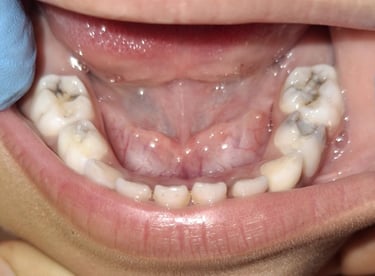

Clinical pictures of teeth requiring RCT

All images are of real cases of teeth where Root canal treatment was performed to remove infection and preserve the natural tooth restoring normal chewing and function of teeth.